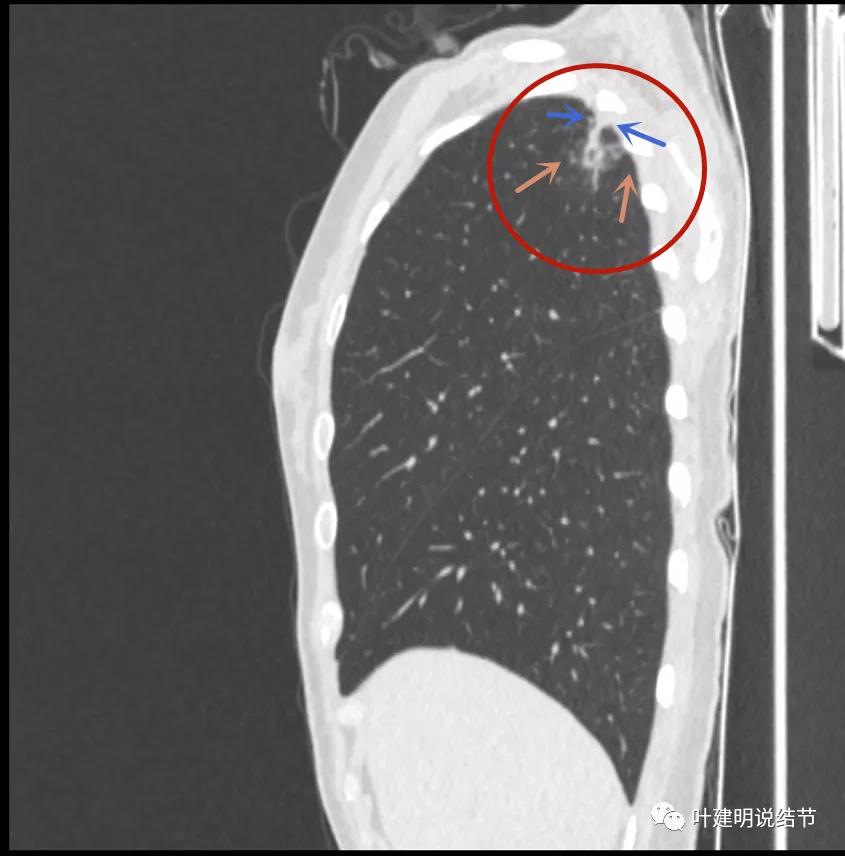

我们再来瞧瞧冠状位与矢状位的图像:

有卫星灶,且条索状(绿色箭头),囊壁密度过高(粉色箭头);有空腔征(黄色箭头)

邻近胸膜增厚明显(蓝色箭头),病灶边上部分有淡磨玻璃(砖色箭头)

病灶与胸壁间不似毛刺,像炎性粘连(相连的结构粗细均匀,没有离开病灶后变细,密度较高,邻近胸膜也增厚的);有卫星状(绿色箭头);有淡且散的边缘不清的磨玻璃成分(砖色箭头)